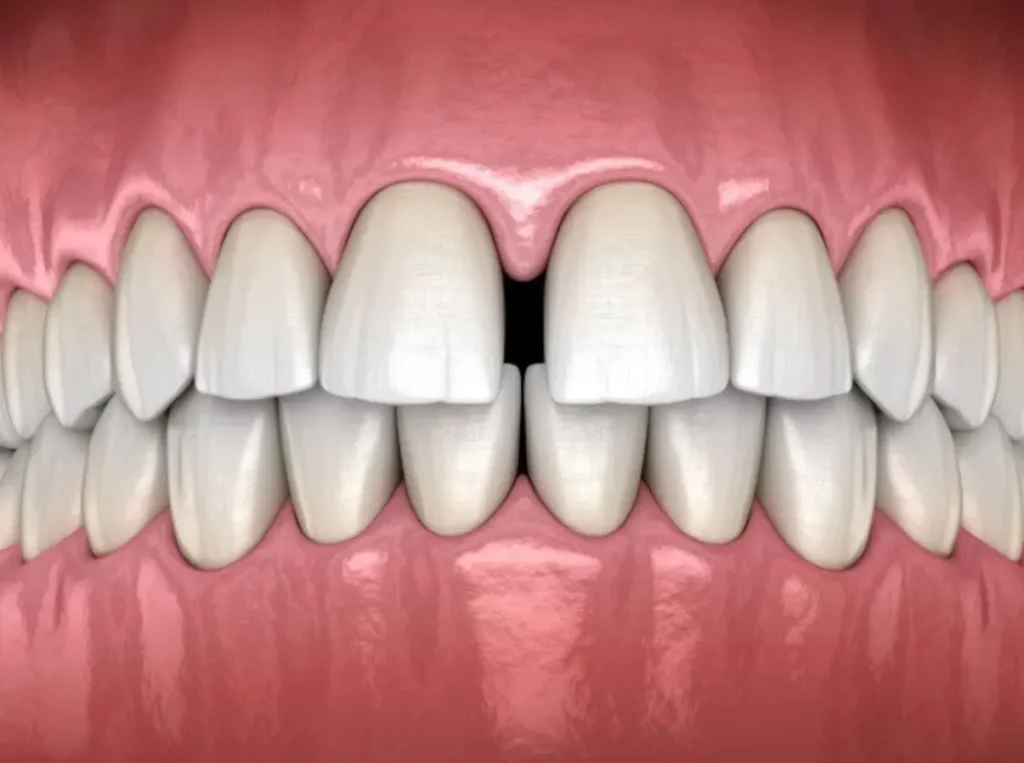

Desde la infancia, el frenillo labial puede presentar un desarrollo anómalo, manifestándose como un frenillo hipertrófico o de inserción baja. Esto puede provocar un espacio interdental mayor al normal, conocido como diastema, y afectar tanto la estética dental como la funcionalidad bucal.

Tener un frenillo en la boca es completamente normal. Sin embargo, si causa dificultad al hablar, comer o provoca separación entre los dientes, puede ser necesario evaluarlo con un dentista. En algunos casos se recomienda una frenectomía para mejorar la funcionalidad y la estética.